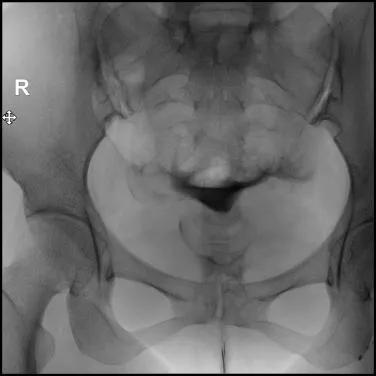

9.在注入对比剂后的20分钟或24小时再拍一张弥散片,视察对比剂在盆腔的弥散情况,分析宫颈、子宫、输卵管的形态特征;

充盈片

弥散片